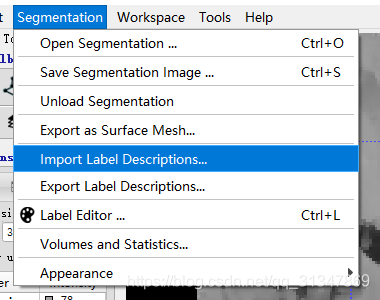

额外导入标签文件:Segmentation -> Import Label Descriptions

Browse 选择标签文件:

需要创建自己的 label,只需要在 label editor 中改变已存在的 label 或新建 label

保存自己的 label 设置,选择导出即可